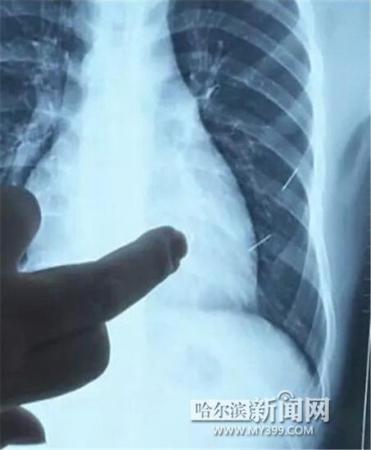

醫(yī)生指出X光片上的針狀物

昨日上午,記者在哈醫(yī)大二院第八住院部心外三病房找到了躺在病床上痛苦不堪的董立仁,家屬正在他身旁不斷安慰著他。見(jiàn)記者前來(lái),董立仁母親李百燕拿出一張X光片,上面可以清晰地看到胸腔內(nèi)一共有4根針狀物,其中一根在心臟部位,兩根在胸腔壁上,還有一根在腹腔壁上。

心外三病房董立仁的主治醫(yī)生告訴記者,董立仁送到醫(yī)院時(shí)病情很危險(xiǎn),隨時(shí)可能危及生命。“通過(guò)檢查發(fā)現(xiàn),他心臟內(nèi)有一個(gè)金屬異物,正好在心臟上。心臟每次跳動(dòng)都與其產(chǎn)生摩擦,導(dǎo)致出血,心包積液懷疑是血液。如果大量出血會(huì)凝結(jié)成血塊,血塊包裹住心臟就會(huì)影響心臟跳動(dòng),隨時(shí)都有停跳的危險(xiǎn)。心臟上的異物是致命傷,其余胸腔壁和腹腔壁的異物傷害不大?!?/p>

昨天16時(shí)30分左右取針手術(shù)開(kāi)始。因鋼針隨時(shí)會(huì)危及患者生命,此次手術(shù)定義為大型手術(shù)。開(kāi)胸后,醫(yī)生打開(kāi)董立仁心包,發(fā)現(xiàn)一枚鋼針已深深扎入心臟,僅露出1厘米長(zhǎng)度在外。拔出鋼針后,醫(yī)生發(fā)現(xiàn),這枚針長(zhǎng)達(dá)5厘米。受鋼針影響,心包出現(xiàn)大量積液,近800毫升。

隨后,在下胸壁位置,第二枚鋼針順利取出。在尋找另兩枚鋼針過(guò)程中,普外、胸外多名醫(yī)生也參與手術(shù),為主刀醫(yī)生提供更為穩(wěn)妥的處理建議。根據(jù)X光片顯示位置,醫(yī)生未在患者體內(nèi)找到剩余兩枚鋼針。醫(yī)生懷疑,其中一枚鋼針可能深藏在肋骨骨膜位置,無(wú)法尋找,最后決定結(jié)束手術(shù),做進(jìn)一步觀察,研究下一次手術(shù)方案。